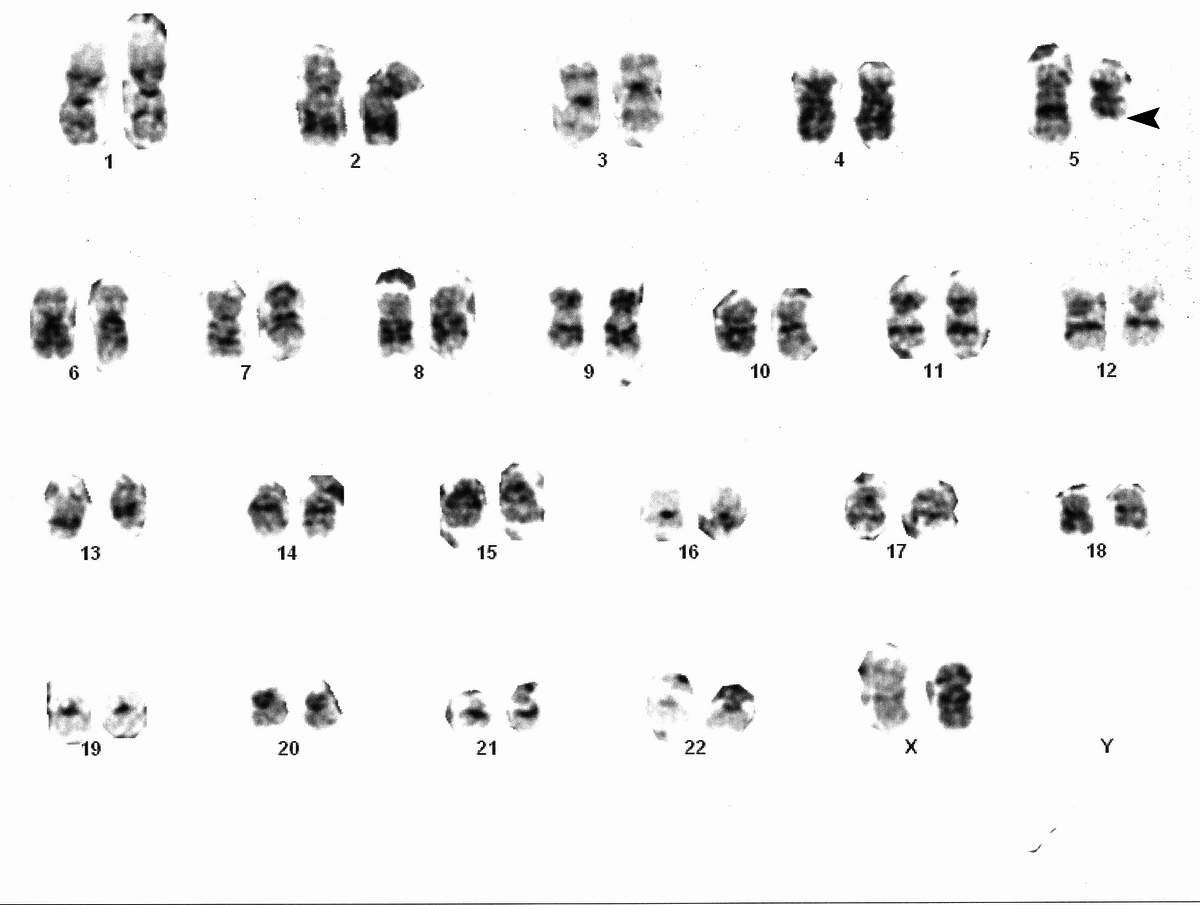

46, XX, del(5)(q13q33)

| Karyotype on bone marrow aspirate showing deletion of long arm of chromosome 5 (5q-)(arrowhead) | ![]() |